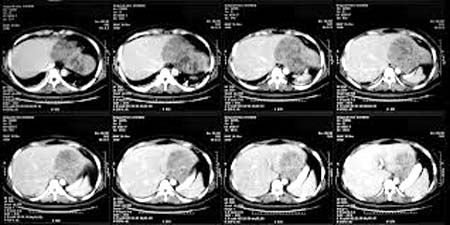

Trả lời:Một câu hỏi và xin tư vấn vô cùng thú vị và có thể là kinh nghiệm của nhiều bệnh nhân khác, xin cảm ơn bạn rất nhiều và liên quan đến câu hỏi này, chúng tôi xin phúc đáp như sau: Với hình ảnh abces gan trên gan không do sán lá gan thường là do con đơn bào amip hay Entamoeba histolytica, loại này thường nhiễm từ đường tiêu hóa sang và sau đó còn gây abces một số cơ quan khác nữa chứ không nhất thiết phải là gan như phổi, não, lách và cả thận, cơ,....song gan vẫn là tạng thường bị thương tổn nhiễm trùng nhiều nhất và các thầy thuốc lâm sàng hay gặp.

Liên quan đến xét nghiệm sán lá gan âm tính, mà có tổn thương gan, rất tiếc chúng tôi không nhìn thấy hình ảnh thương tổn gan trên siêu âm và trên CT scanner của bạn, nên sẽ khó đoán được có phải sán lá gan hay là amip nên cũng không tiên lượng được thời gian lành của bạn đối với abces gan là bao lâu (vì bạn lưu ý rằng không phải bị sán lá gan lúc nào xét nghiệm cũng dương tính, chúng tôi chưa thống kê đầy đủ, song vẫn có một tỷ lệ nhỏ < 3% là tổn thương gan có nhưng ELISA lại âm tính là bình thường vì còn liên quan đến giai đoạn làm xét nghiệm, đặc hiệu từng bộ kít chẩn đoán miễn dịch, cũng như kháng thể đặc hiệu loài Fasciola hepatica hay Fasciola gigantica,…